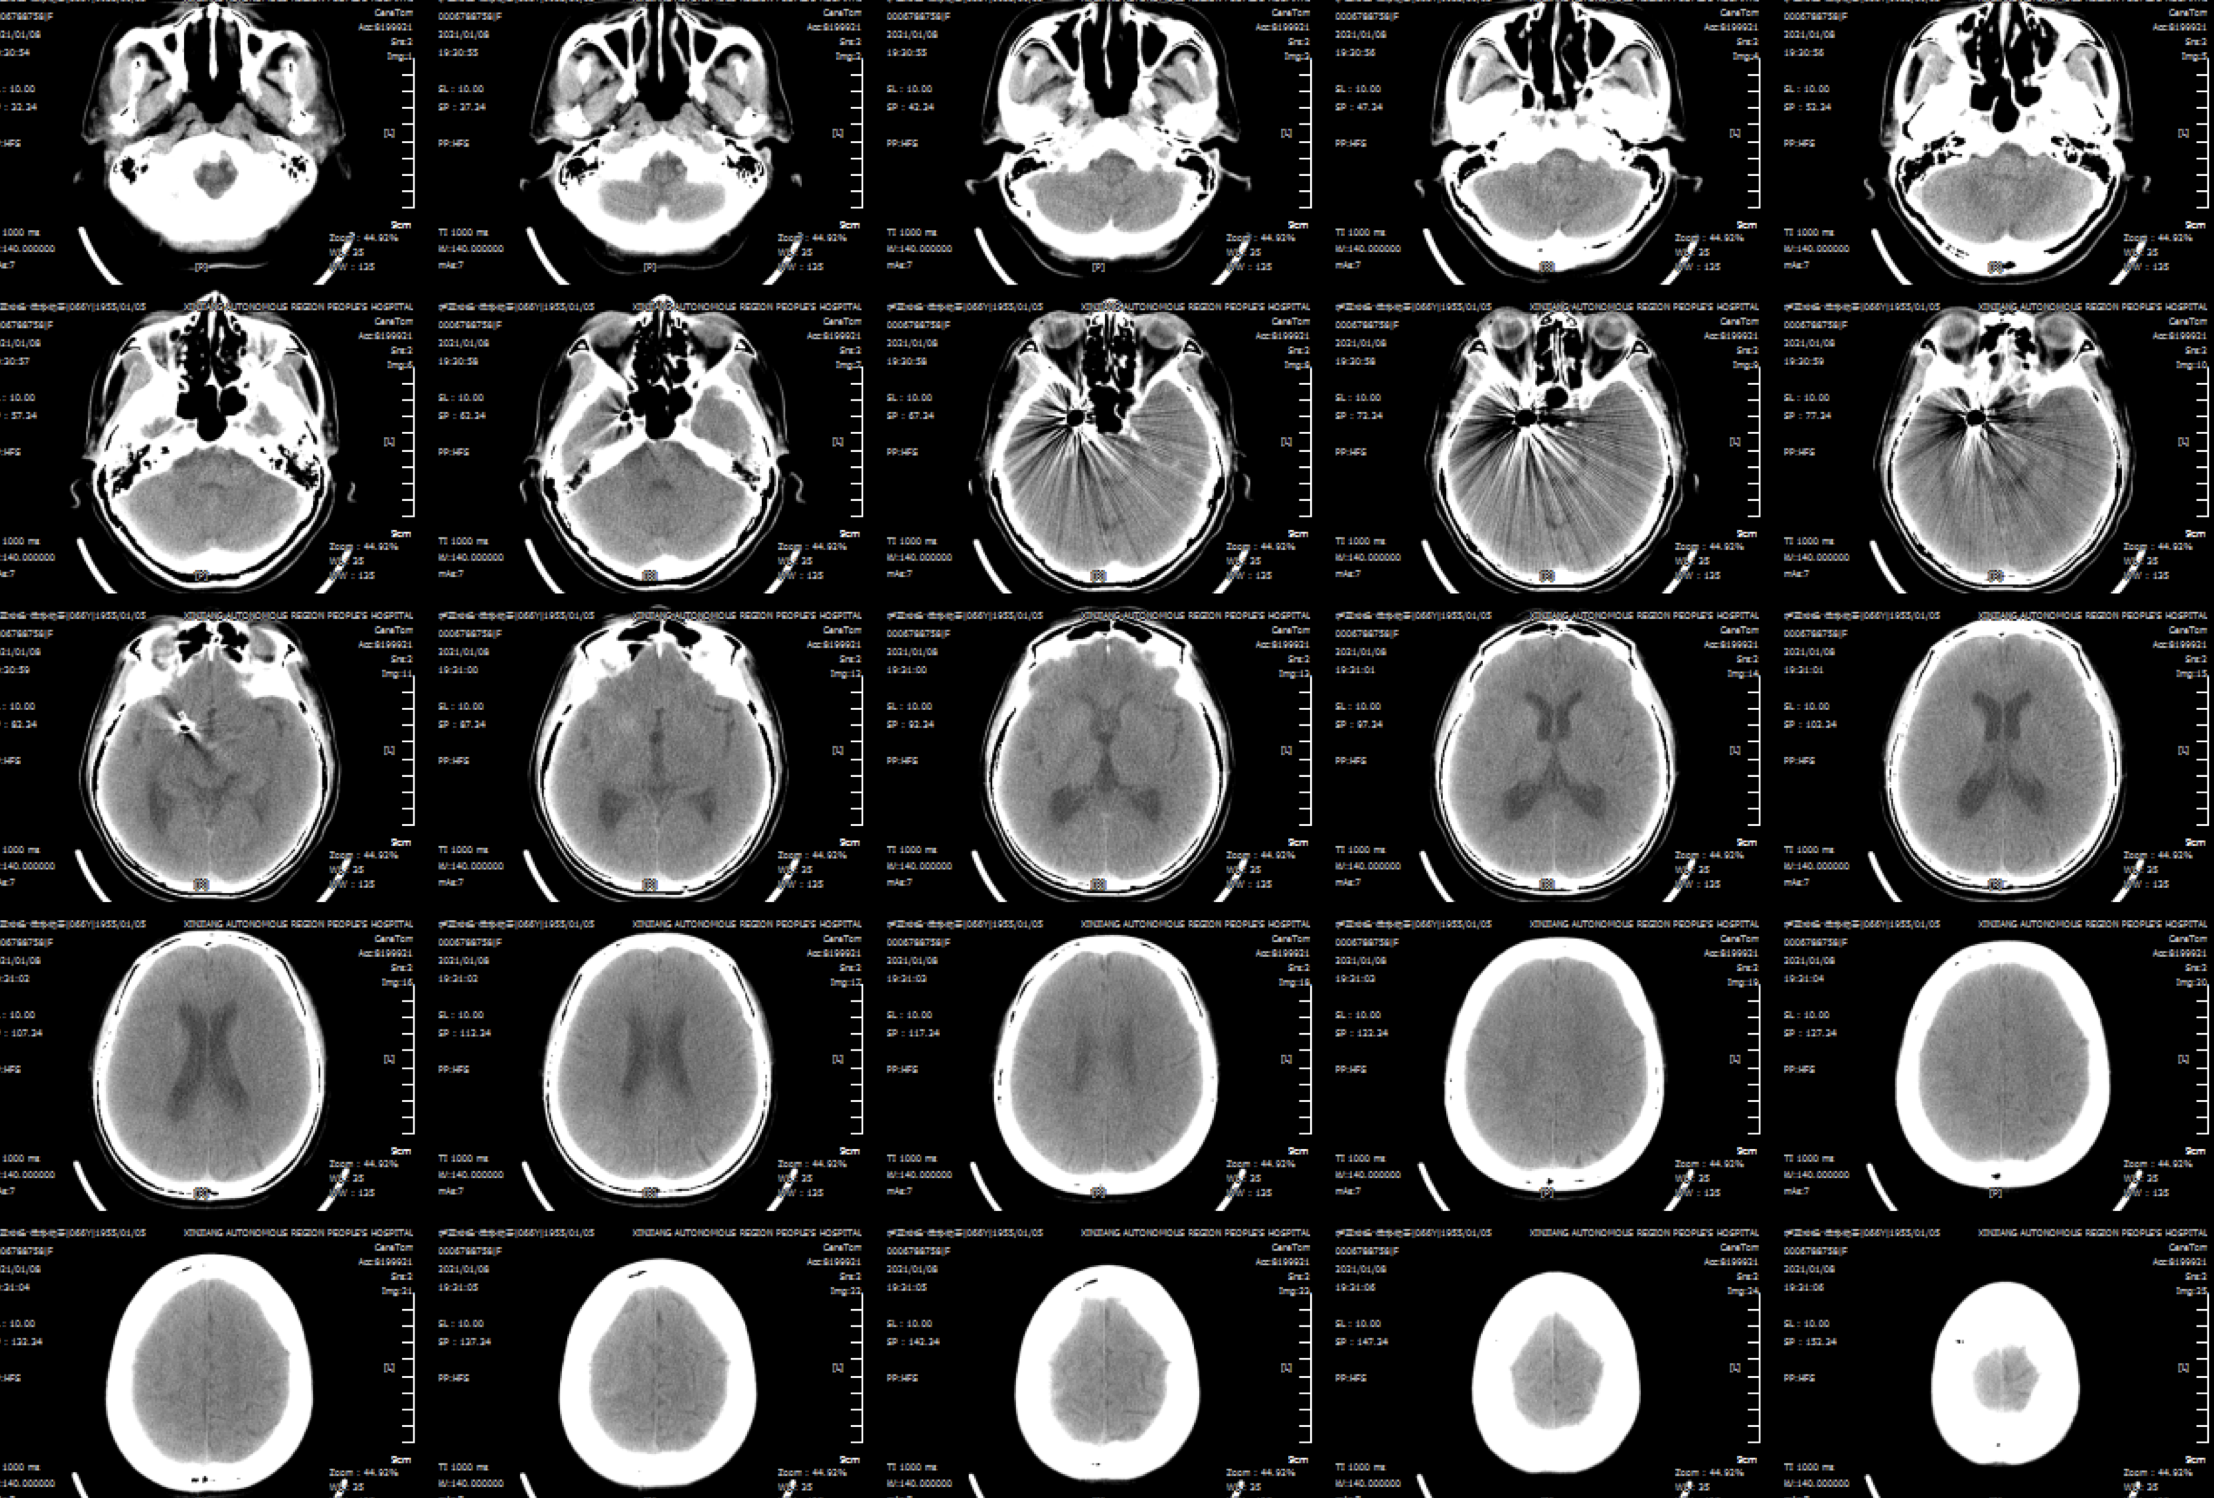

入院后完善头颅CTA:右侧颈内动脉后交通动脉瘤。

后交通动脉瘤大小约22mm*12mm。

朮后第二天复查头颅CT:颅内未见明显异常!